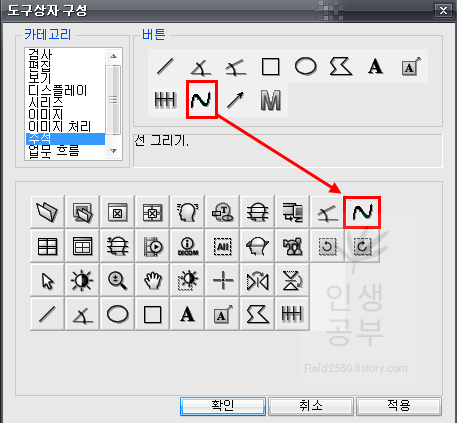

저 같은 경우는 선을 그리는 버튼도 많이 사용하니 추가해 줍니다.

카테고리에서 주석 메뉴를 클릭하면 오른쪽 버튼칸에서 2번째줄 2번째에 있는 것이 선그리기입니다. 위와 같은 방법으로 아래 도구상자란에 마우스로 끌어서 추가해줍니다.

목의 정렬을 알아보기 위해서 목뼈의 선들을 연결해서 그어보는 방법에 대해서 알아보겠습니다. 도구 상자에서 빨간색네모상자 안에 있는 물결무늬 모양의 버튼을 눌러줍니다.